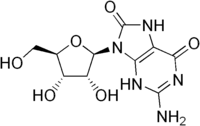

| IUPAC name

2-Amino-9-[(2R,3R,4S,5R)-3,4-dihydroxy-5-(hydroxymethyl)-2-tetrahydrofuranyl]-3,7-dihydropurine-6,8-dione | |

8-Oxoguanosine | |

| C10H13N5O6 | |

| Molar mass | 299.24 g/mol |

8-Hydroxyguanosine is an RNA nucleoside which is an oxidative derivative of guanosine. Measurement of the levels of 8-hydroxyguanosine is used as a biomarker of oxidative stress causing RNA damage.[1]